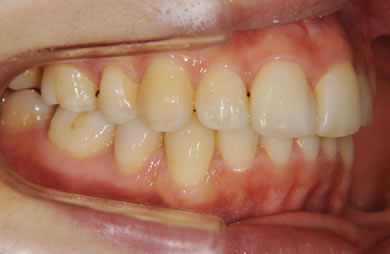

| 性別/年齢 | 女性 / 26歳 | ||||||||||||||||||||||||||||||||

| 主訴 | 上下乱ぐい歯と出っ歯を治したい。 | ||||||||||||||||||||||||||||||||

| 治療方針 | 口元が出ていていること、がたつきが大きいことより、上下左右の第一小臼歯および親知らずを抜歯し、マルチブラケット治療を行う。抜歯した隙間を活用できるよう上顎にはインプラントアンカー(釘)を使用し、その釘より歯を後ろに移動する。 | ||||||||||||||||||||||||||||||||

| 治療内容 | 唇側矯正(シルバー)、矯正用スピードインプラント、ハイブリッドセラミックインレー2本 | ||||||||||||||||||||||||||||||||